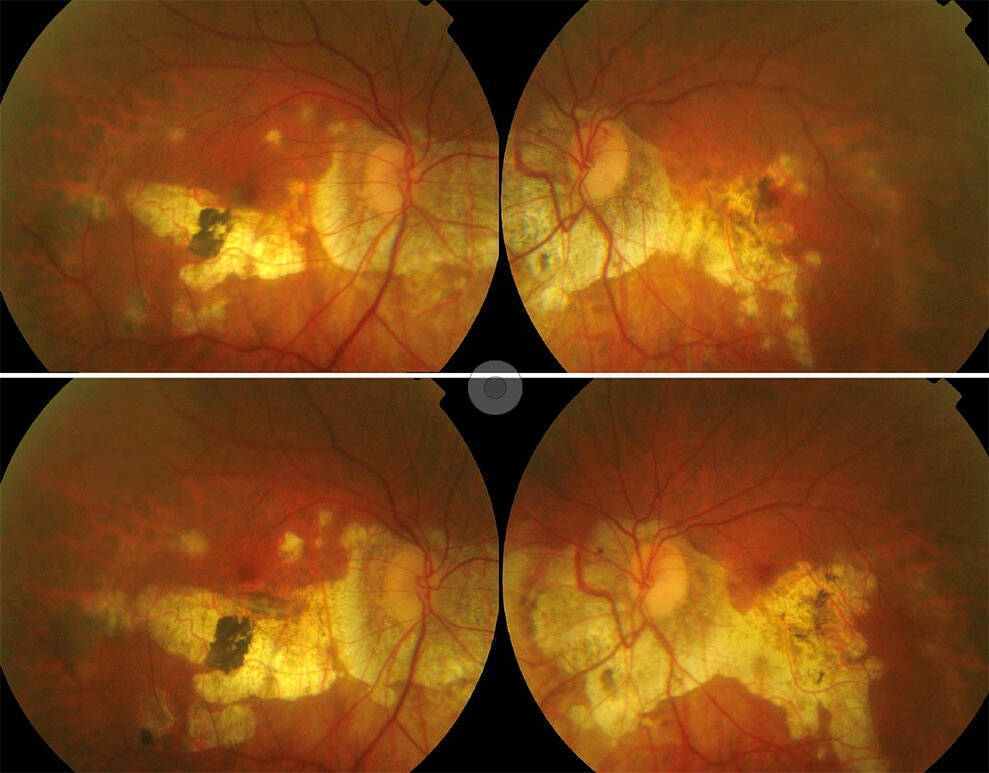

Figure 3. Imagerie multimodale d’une patiente de 34 ans atteinte de PIC. Le panneau (A) montre une photographie en couleur du fond d’œil d’un œil à aspect myopique, présentant des zones d’atrophie en plaques et de multiples lésions de PIC. (B) L’angiographie à la fluorescéine révèle plusieurs foyers hyperfluorescents au pôle postérieur. Le panneau (C) montre une coupe OCT à travers ces zones : en position sous-fovéolaire (pointe de flèche), on observe une lésion active caractérisée par un dédoublement du complexe membrane de Bruch–EPR, une rupture de la membrane de Bruch, une hypertransmission choroïdienne et un épaississement choroïdien ; à l’inverse, une lésion inactive adjacente (étoile) se caractérise uniquement par une interruption du complexe membrane de Bruch–EPR avec hypertransmission choroïdienne. Le panneau (D) montre une angiographie au vert d’indocyanine en phase tardive, avec une ligne hypofluorescente ramifiée compatible avec des lacquer cracks (étoile). Le panneau (E) montre l’autofluorescence du fond d’œil au niveau du pôle postérieur, où les lésions actives apparaissent comme des zones de légère hyperautofluorescence (pointe de flèche), tandis que la cicatrice atrophique centrale apparaît hypoautofluorescente.